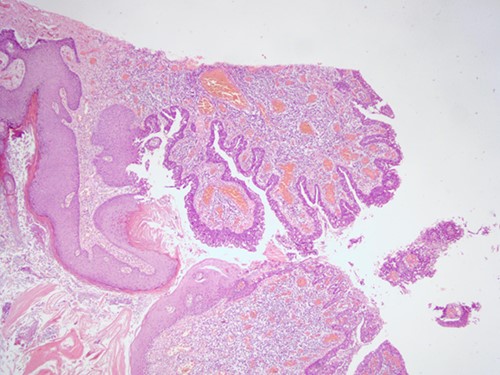

The histopathological examination found cystic invaginations of the infundibular epithelium projecting into the dermis, covered by a double cell layer (Fig. 2), proliferation of glands with prominent papillary architecture (Fig. 3) and fibrous cores containing numerous stromal plasma cells (Fig. 4). Other findings include verrucous (papillomatous) epidermal hyperplasia with hyperkeratosis and hypergranulosis (Fig. 5), irregular duct-like structures and cystic spaces (Fig. 6) and glands with double layer of cuboidal columnar epithelium and numerous stromal plasma cells (Fig. 7). These findings are compatible with Syringocystadenoma papilliferum with no signs of malignancy.

H&E staining, 4× magnification. Cystic invaginations of the infundibular epithelium projecting into the dermis, covered by a double cell layer.